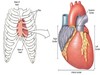

What is seen in the anterior view of the heart?

Right atrium

Right ventricle

What is seen in the posterior view of the heart?

Left atrium

Left ventricle

What is A?

Right ventricle

What is B?

Right atrium

What is C?

Azygos vein

What is D?

Aorta

What is E?

Left atrium

What is F?

Right ventricle

What is A?

Superior vena cava

What is B?

Inferior vena cava

What is C?

Right atrium

What is D?

Right ventricle

What is E?

Left ventricle

What is F?

Left atrium

What is G?

Left pulmonary veins

What is H?

Left pulmonary artery

What is I?

Aorta

What is J?

Right pulmonary artery